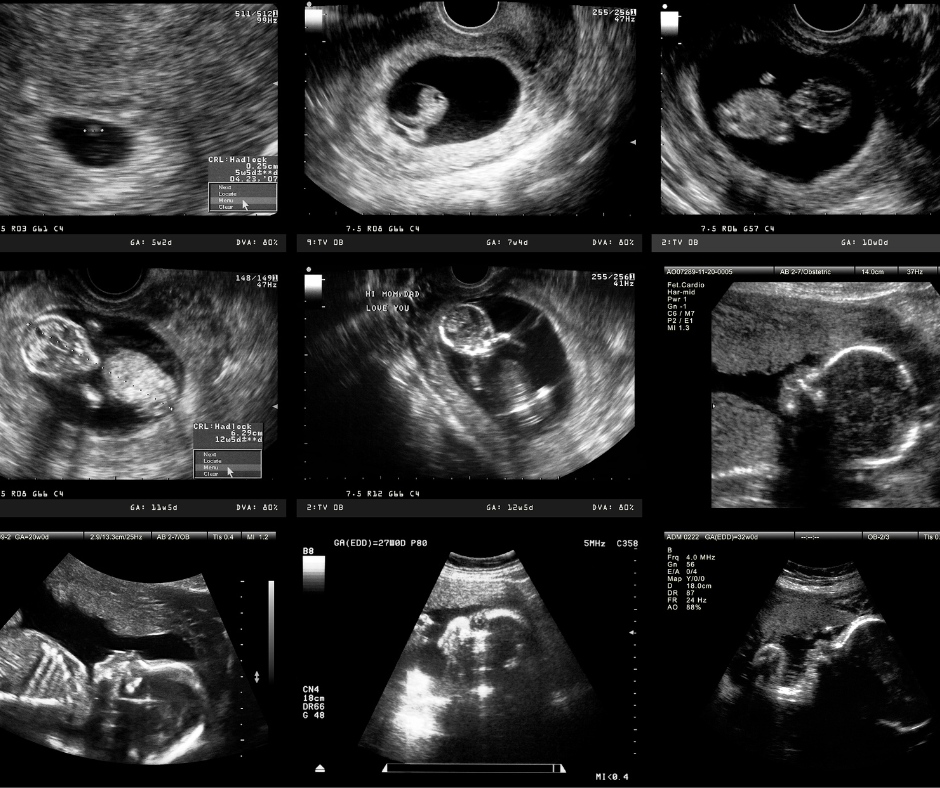

Trong 10% đầu bài viết này, chúng ta sẽ tìm hiểu về Chẩn đoán trước sinh & di truyền, một phương pháp quan trọng đang được nhiều mẹ bầu quan tâm để đánh giá sức khỏe thai nhi ngay từ những tuần đầu. Đây không chỉ là bước kiểm tra y khoa đơn thuần mà còn là cánh tay hỗ trợ mạnh mẽ giúp gia đình đưa ra quyết định chính xác và chủ động trong suốt thai kỳ.

Chẩn đoán trước sinh bao gồm các kỹ thuật y khoa nhằm đánh giá nguy cơ bất thường của thai nhi trong thời kỳ mang thai. Các xét nghiệm này giúp phát hiện:

Siêu âm độ mờ da gáy

Thực hiện từ tuần 11–13, giúp phát hiện nguy cơ hội chứng Down hoặc dị tật tim.

Kết hợp xét nghiệm máu và siêu âm để đánh giá nguy cơ bất thường.